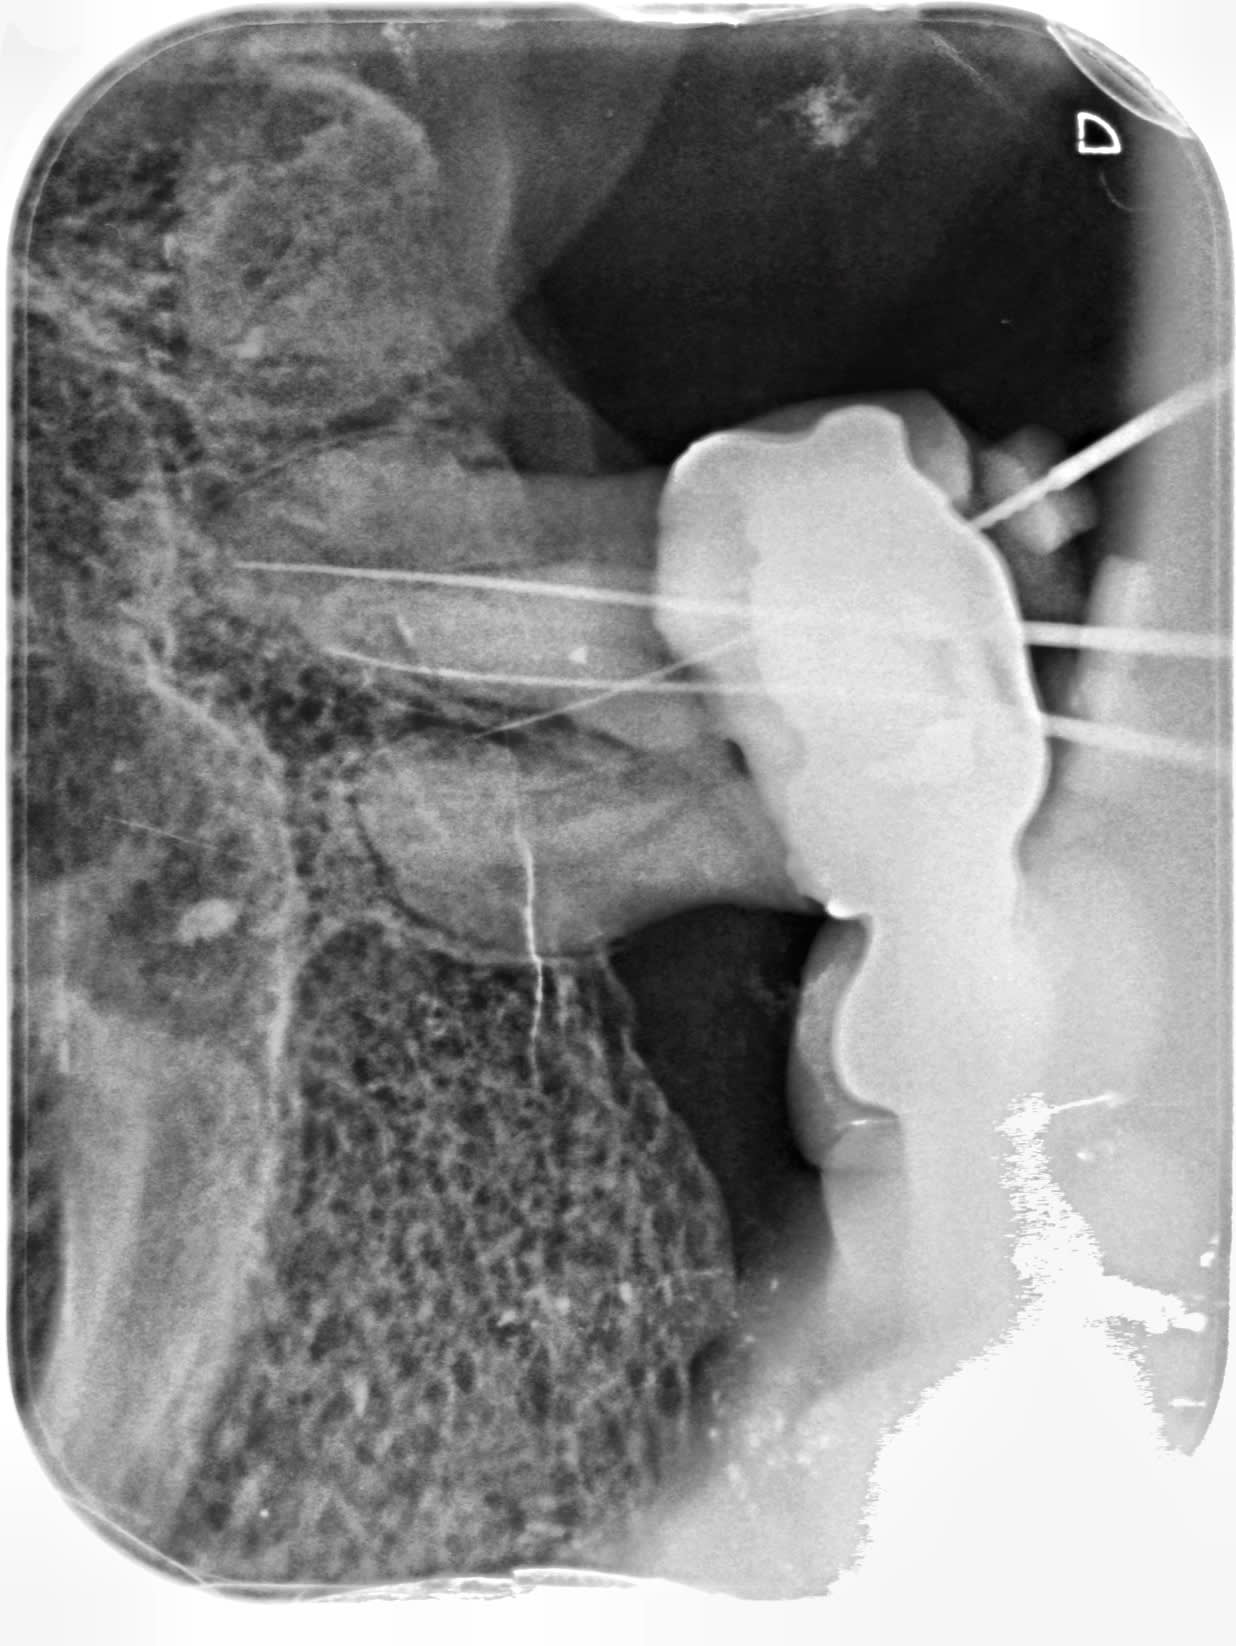

donc là j'avais fait une pulpo sur la 26,

pour me rendre compte que la dent causale était la 27 que j'ai extraite par la suite

malgré des entrés canalaires évidentes la prise de LO est une catastrophe.

à la première radio je pense quez je suis bien sur le DV et mauvais sur le palatin alors que c' est l'inverse

puis j’enchaîne les reprises , recherche de mv ( 1 ou 2) , je m'enfonce et n'arrive plus , ne comprends pas comment je peux retrouver le DV.

Je crois plutôt que tu as surtout travaillé dans la carie... ;)

Cette dent est fichue, tout est carié sous la couronne, tout comme tes films :)))

Oui le bridge n’était vraiment plus étanche,il faut le virer voir si la dent est conservable ou pas parce que l’image donne l’impression d’une atteinte du plancher.

ça ne m'étonnerait pas que tes entrées ''évidentes'' soient des perfs

Cest ce qu'a écrit Hokusai. La carie qui a rompu le plancher pulpaire et faux canaux.

oui mais vous savez quand on fait une perforation, on le sent inconsciemment, différence de resistance dans la rotation, on ressort sa lime pleine de sang, on a un écoulement sanguin qui persiste,hors là il ne me semble pas que cela ait été le cas